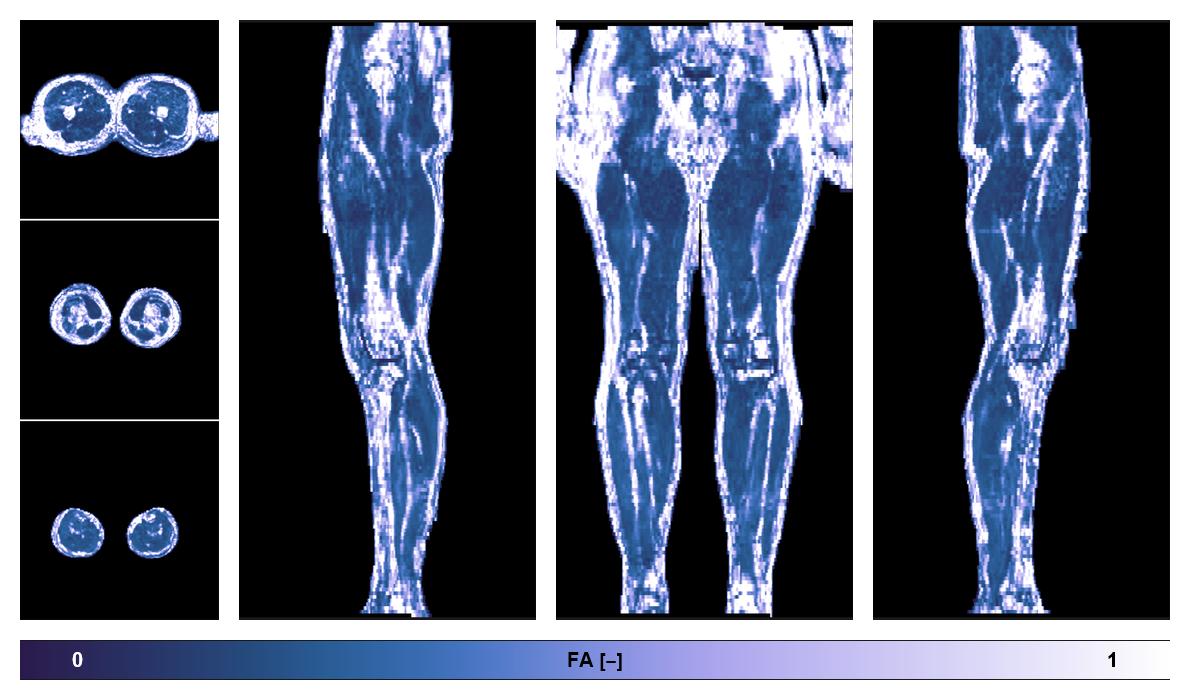

• Fractional anisotropy

IVIM corrected whole leg muscle fractional anisotropy obtained from diffusion tensor imaging.